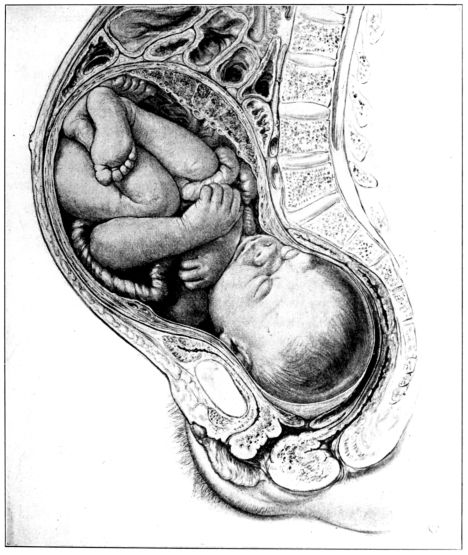

27. Full term fetus in utero 81

The true pelvis, on the other hand, is of greatest possible obstetrical importance since the child must pass through its narrow passage during birth. It lies below and somewhat behind the inlet; is an irregularly shaped, bottomless basin, and contains the generative organs, rectum and bladder. Its bony walls are more complete than those of the false pelvis, and are formed by the sacrum, coccyx and innominate bones. Its lower margin constitutes the outlet, or inferior strait, and being longer in its antero-posterior dimension than in its transverse measurement, its long axis is at right angles to the long axis of the inlet. (Fig. 3.) A baby’s head, accordingly, must twist or rotate in making its descent through this bony canal, for the long diameter of the head must first conform to one of the long diameters of the inlet, either transverse or oblique, and then turn so that the length 24of the head is lying antero-posteriorly, in conformity to the long diameter of the outlet, through which it next passes.

Thus it becomes apparent that the structure of the pelvis requires the child’s head, not only to rotate in its passage through the birth canal, but also to describe an arc, since the part of the head which passes down the posterior wall travels farther in a given time than the part which passes under the pubis.

This twisting and curving of the birth canal must be appreciated in order to understand the mechanism of labor.